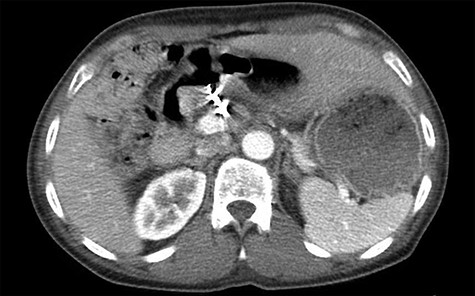

Three years later, the patient presented to the emergency department with epigastric pain as well as melena. The patient could not remember the last time he took any acid suppression medication. He had increased his intake of ibuprofen. The patient was found to have a Hgb of 6.5 g/dl. He was given 2 U of PRBC and was taken to the endoscopy suite by the gastroenterology team. The endoscopy demonstrated a posterior duodenal bulb ulcer with a metallic ring in the center (Fig. 3). At this point, the general surgery team was consulted. A computed tomography scan of his abdomen and pelvis was obtained to further guide our operative decision-making (Fig. 4).

Single axial view of subsequent computed tomography scan demonstrating scattering from GDA coil with associated area suspicious for ulcer in duodenal bulb